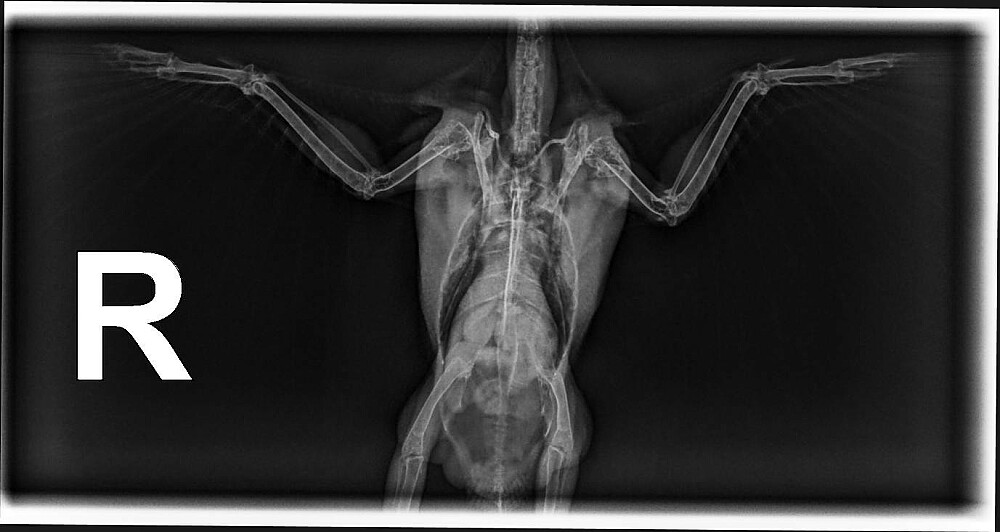

Depending on how stable the patient is, radiographs (x-rays) may be taken immediately or delayed briefly to allow time for stabilization. These diagnostics are essential, as window strikes often result in injuries that are not visible externally, most commonly fractures of the clavicles (similar to collarbones in humans), as well as internal trauma and ocular damage. If injuries are identified, treatment begins right away. Patients are typically started on anti-inflammatory pain medication and supportive fluid therapy, followed by strict cage rest to allow for healing.

Throughout rehabilitation, our Wildlife Technicians maintain detailed medical records and schedule regular rechecks, including repeat examinations and x-rays to monitor progress. After approximately three weeks, follow-up radiographs are performed. If healing is progressing well, the patient is gradually moved into a larger enclosure to allow for increased movement. The next stage of recovery takes place at our Parkland County rehabilitation facility, where patients spend additional time in larger spaces rebuilding strength, improving flight ability, and practicing natural behaviors essential for survival. At around 6–8 weeks, a final release assessment is conducted. If the bird meets all criteria, it is released back into the area where it was found or into another suitable habitat.